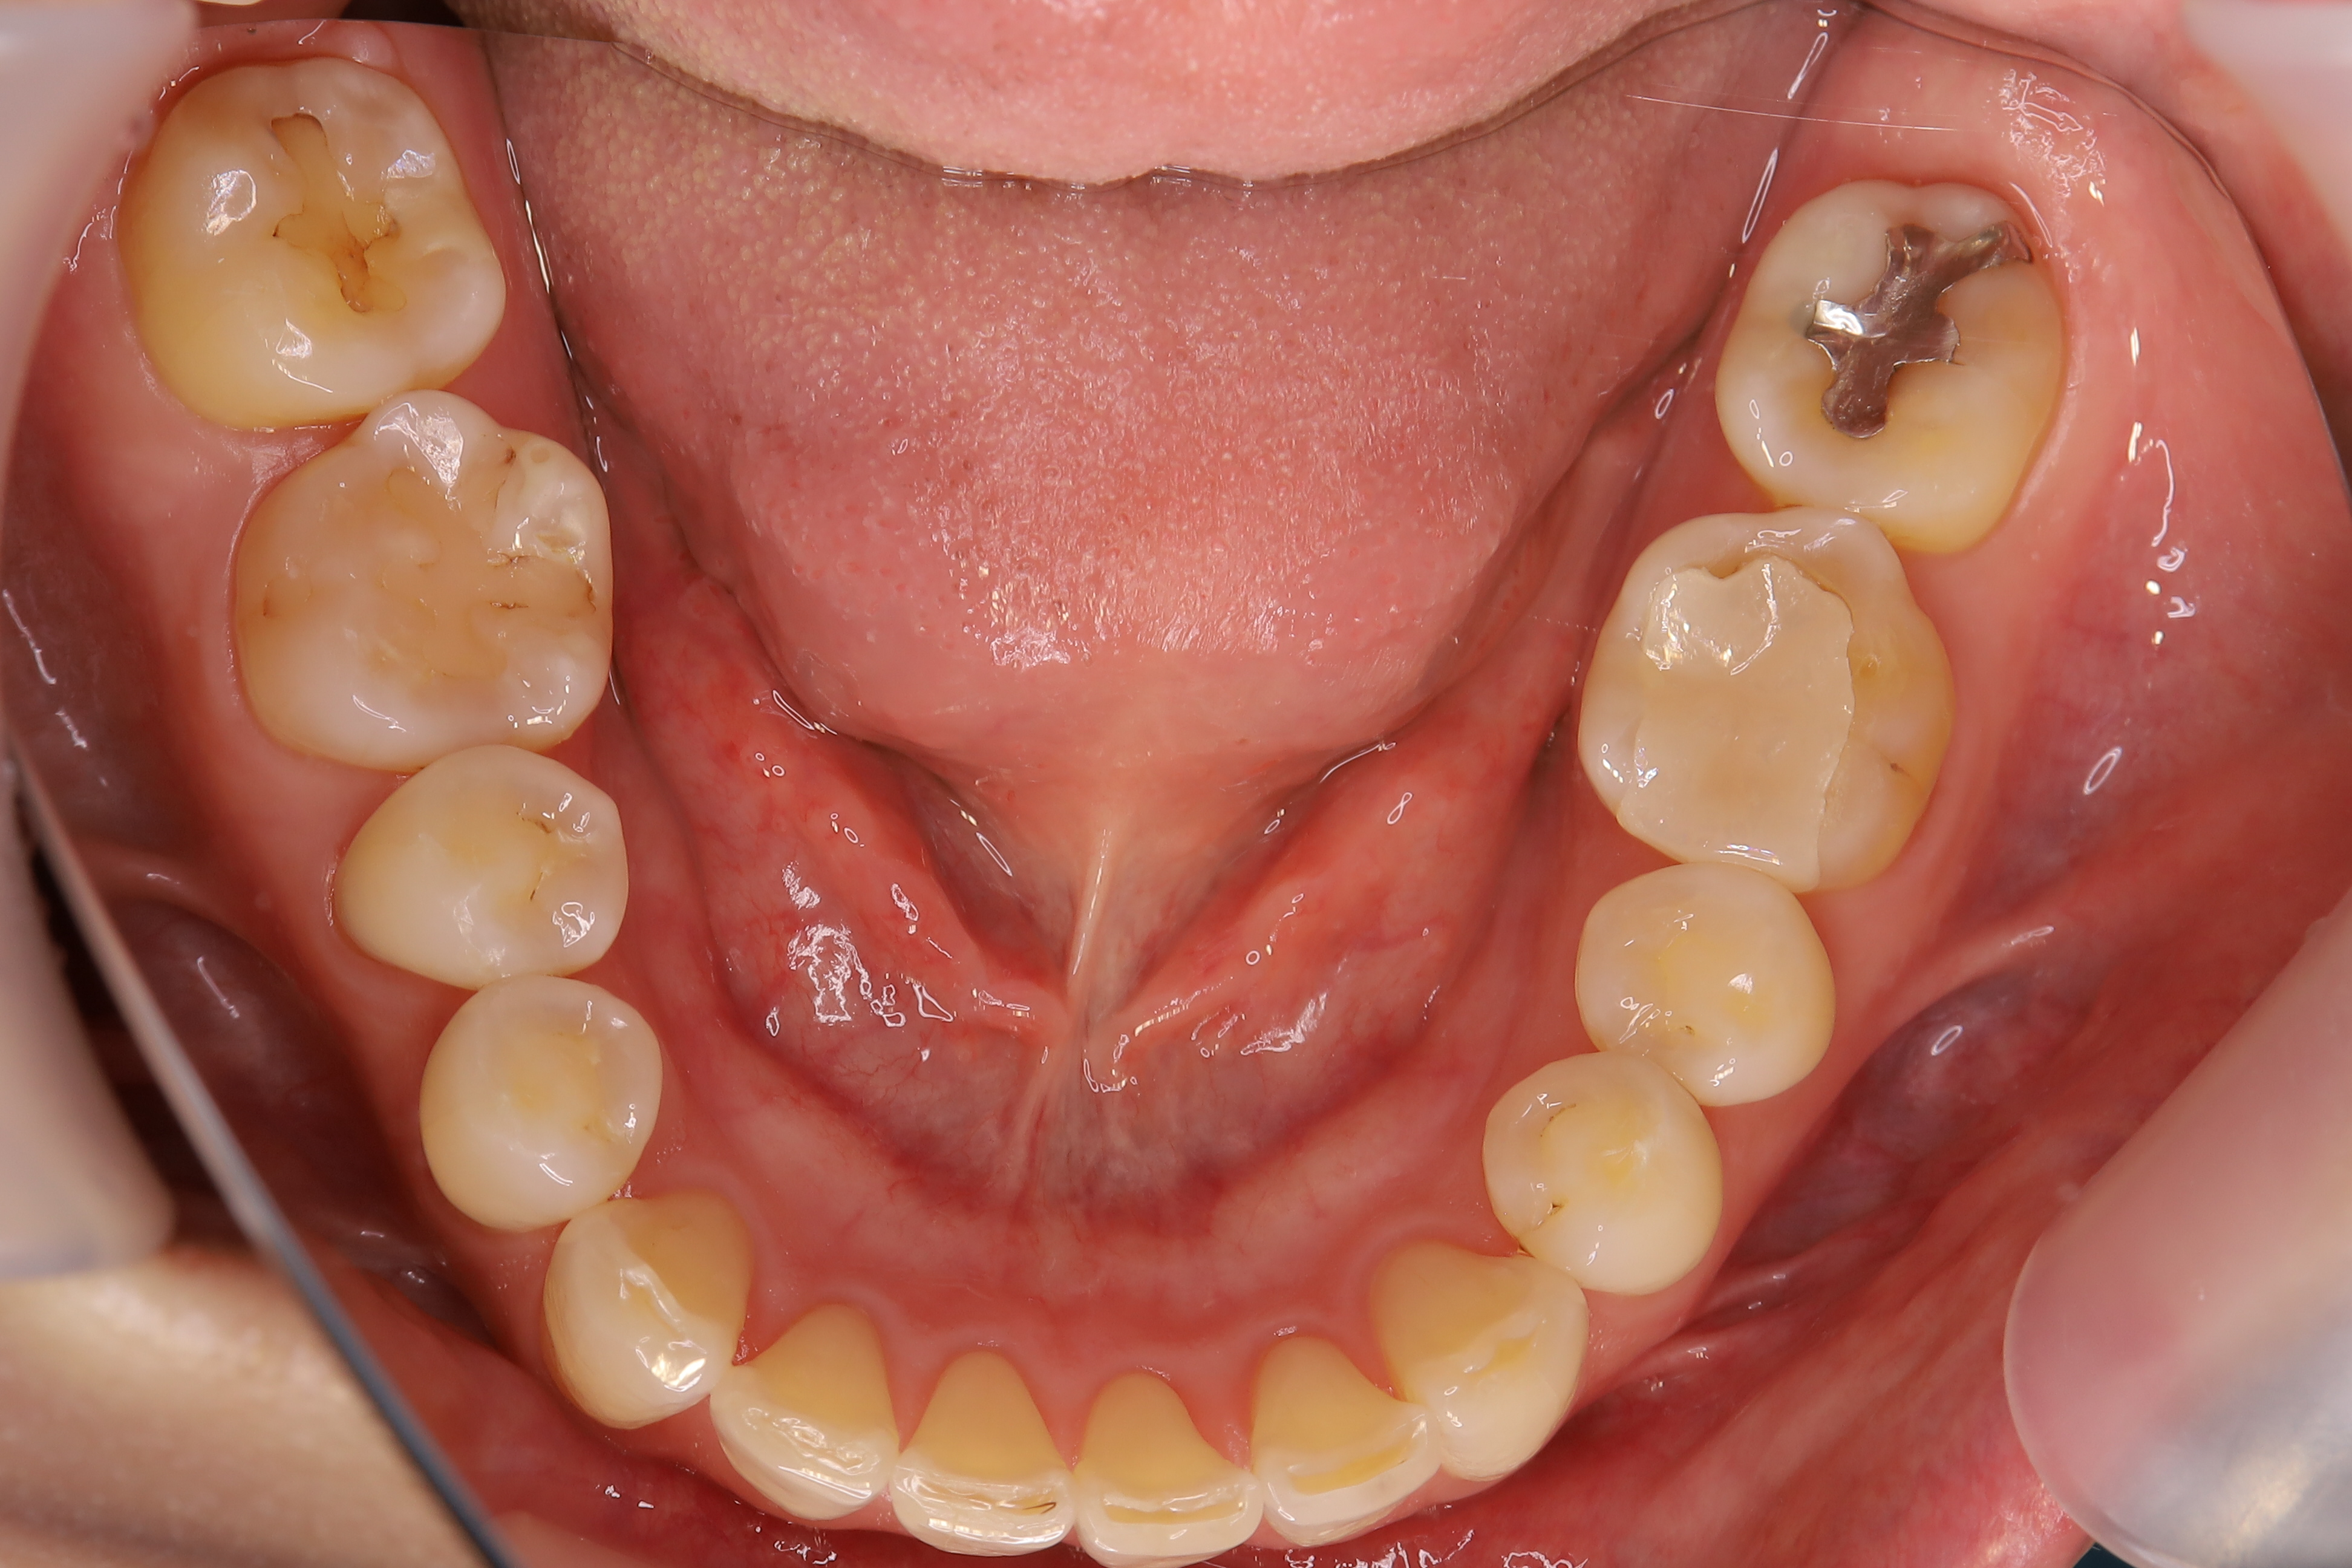

審美歯科治療

症例紹介